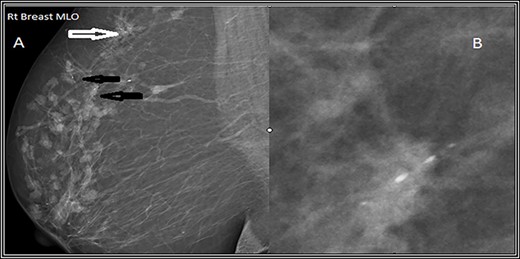

Mediolateral oblique (MLO) mammographic view of the right breast. (A) Shows multiple foci of microcalcifications arranged in linear distribution (black arrows) and others in clusters (white arrows). (B) Spot magnification view of the most suspicious lesion shows linear fine microcalcifications.